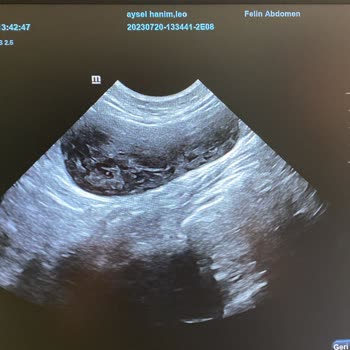

Nachdem ich dieses Futter meiner Katze gegeben hatte, wurde sie krank. Ich brachte sie zum Tierarzt, der eine Lebensmittelvergiftung diagnostizierte und sagte, dass sie vom Nassfutter stamme. Nach zwei Injektionen kehrten wir nach Hause zurück. Als es meiner Katze schlechter ging, brachte ich sie er...